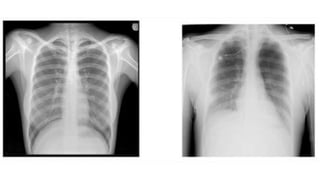

PREVIOUS CXR • PreviousCXRS your best friend. You see a real or possible abnormality on the CXR. • Was it there before? Has it got larger or smaller? Is it unchanged? • A previous CXR will often highlight an important but subtle change. • On the other hand it will frequently provide reassurance that all is well.